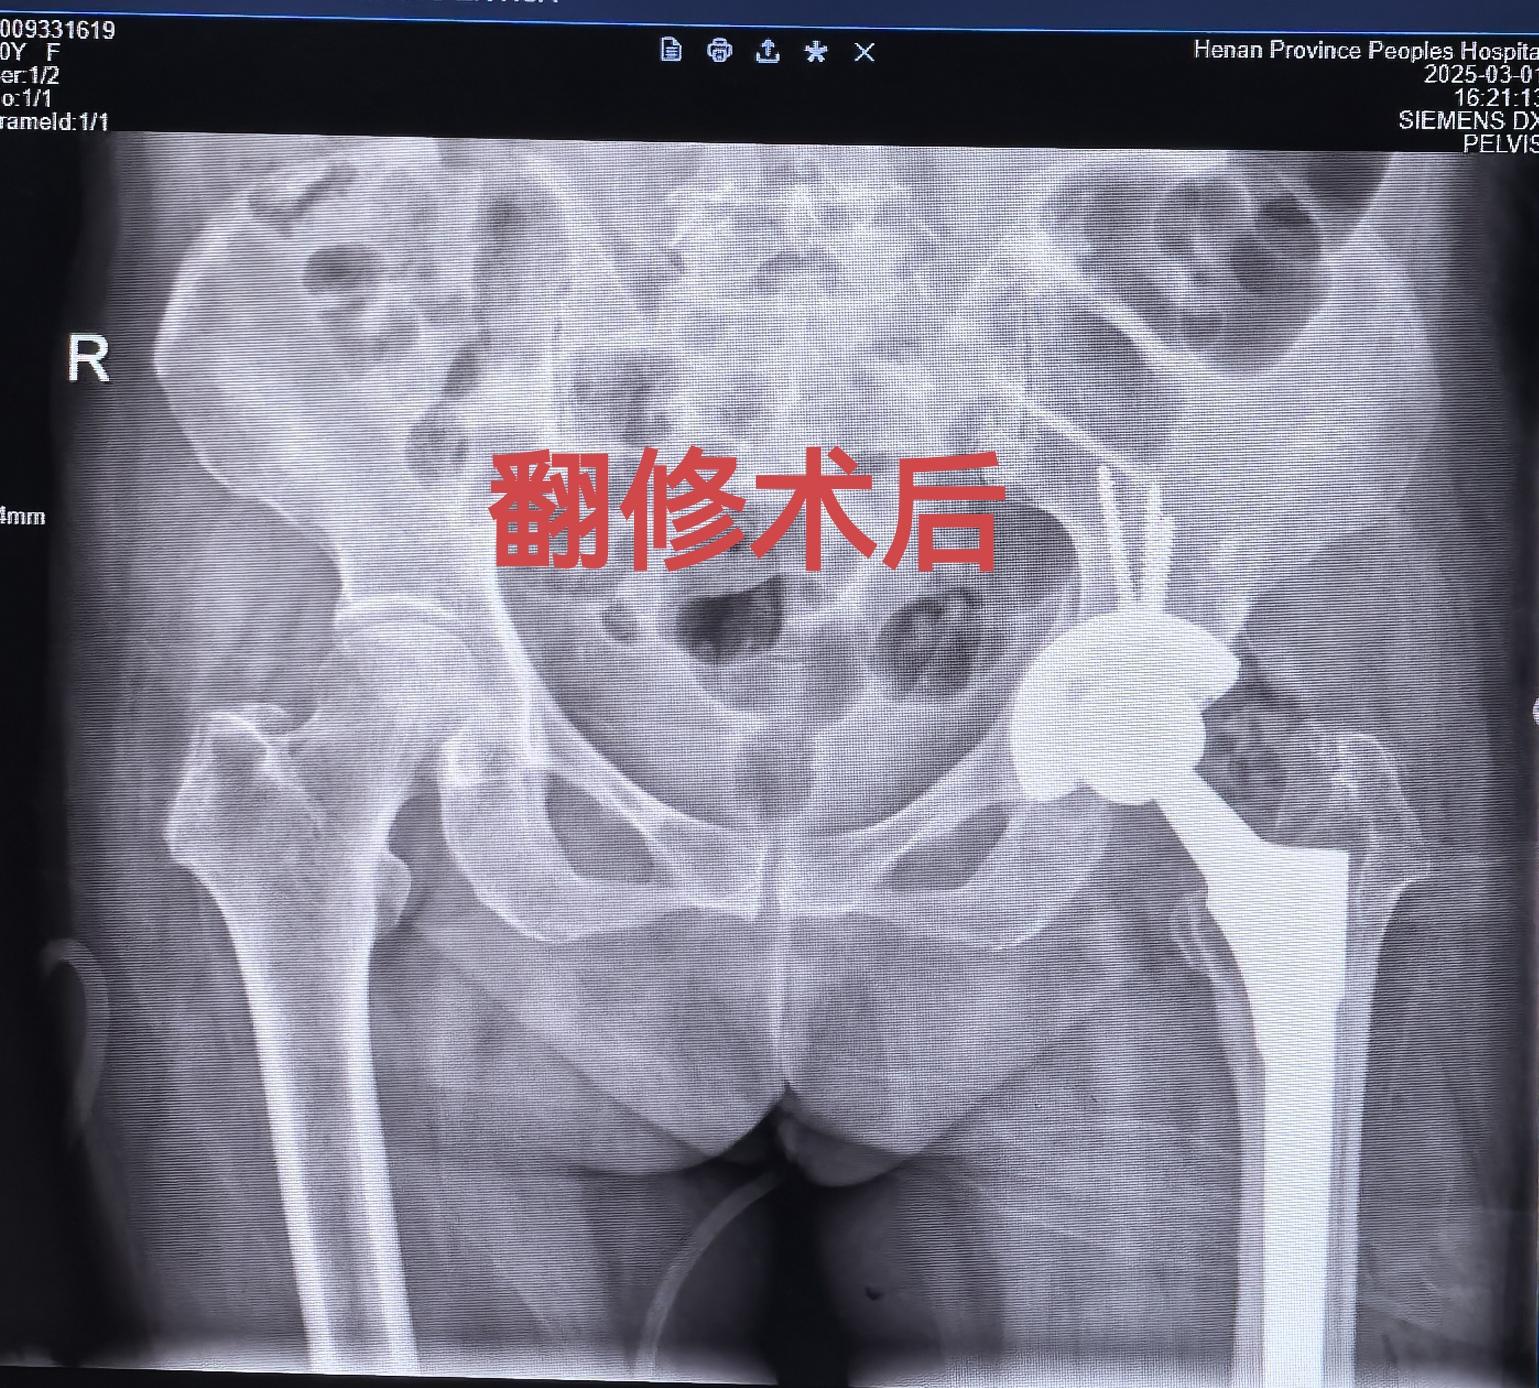

髋关节翻修,髋关节置换。股骨头坏死髋关节置换术后22年假体松动,83岁高龄二次翻修,手术顺利,再次“续命”20年🌹